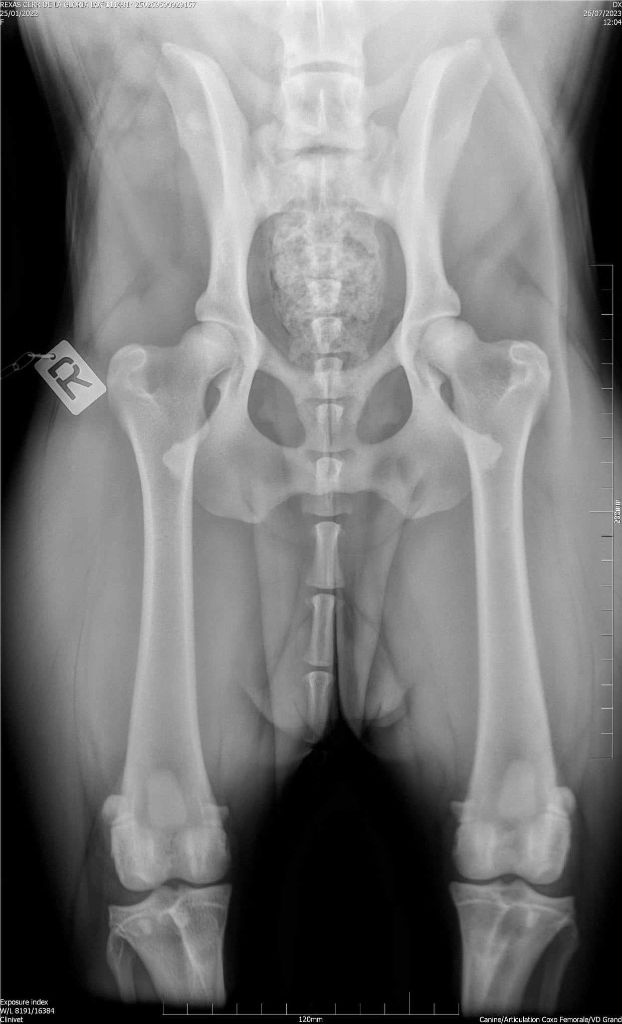

radio hanche